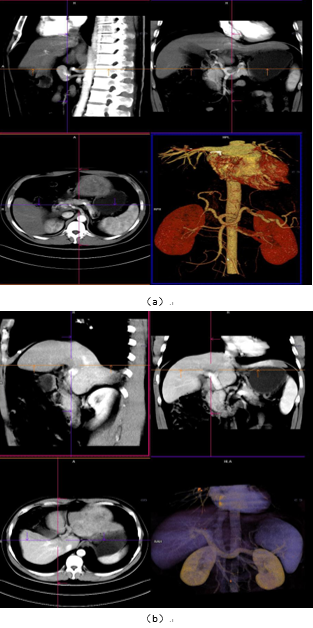

图1成像方式是目前大多数医院常规采取的扫描方式,满足对疾病的诊断,我中心当前采用的也是此类扫描方式,主要适用于常规检查、诊断,临床需求不单纯是提供诊断、还需要了解病灶与比邻组织器官关系,尤其是与大血管间的关系,制定最优化的手术方案,更快捷、安全、有效的进行手术治疗,但普通扫描在血管区分上欠佳。图2-9为肝脏CT一体化成像图,能更好的区分肝动脉、门脉、胆总管等结构,加上延迟扫描对正常组织器官及病变的显示影响有限,结合3D可视化图像,为临床医师手术提供精准化的参考、制定精准化的手术路径,为患者减少术后并发症。

图1:中心常规肝脏CT增强动脉、门脉显像(VRT/MPR)

图2:一体化成像扫描肝动脉、门脉显像(VRT/MPR)

9:肝脏3D可视化